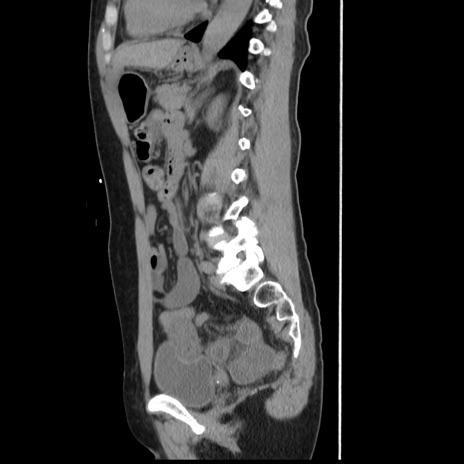

症例10(矢状断像)

【症例】 50歳代女性

【主訴】 腹痛

【現病歴】前日生レバーを食べた。今朝に排便あり。 昼前に突然発症の腹痛を生じ、当院救急外来を受診した。

【既往歴】 子宮筋腫にてで子宮全摘後

【身体所見】 意識清明、腹部:平坦、軟、下腹部やや左を中心に圧痛・反跳痛あり、筋性防御あり

【データ】WBC 7800、CRP 0.07